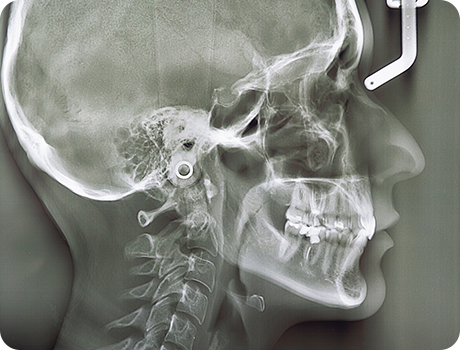

精度の高い診断があってこそ、安全性が高く、効果が期待できる治療の提供が可能となります。

当院では、歯科用CT、頭部専用のセファログラム、デジタルレントゲン、口腔内スキャナーなど、

先進的な設備機器が充実しており、精密な検査、高精度の診断に役立てています。

歯科用CT

セファログラム